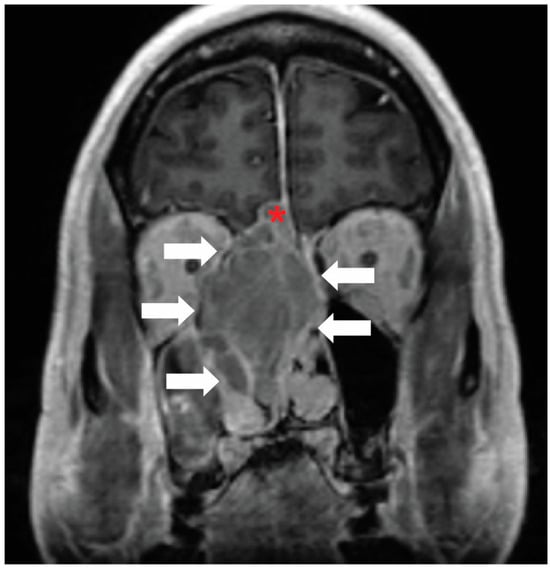

Figure 2.

Classical tumor visualization: Contrast-enhanced coronal MRI of the face demonstrates an esthesioneuroblastoma in the right ethmoid air cells (white arrows). There is also intracranial extension (red asterisk). Image and annotations are from the authors.